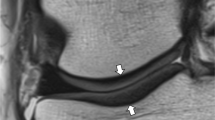

Sagittal FS IW MR images at the level of the lateral femoral condyle in a a 46-year-old asymptomatic male volunteer and b a 35-year-old asymptomatic female volunteer showing a normal inter-individual variation of cartilage thickness (between arrowheads), and physiological areas of cartilage thinning overlying the lateral femoral condylar notch (white arrows), the posterior lateral femoral condyle (arrowheads), and at the margins of cartilage (thin arrows)